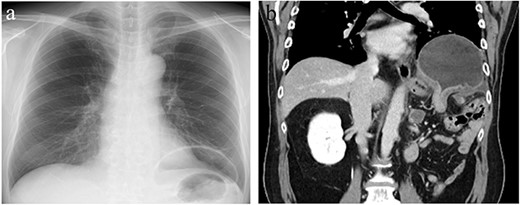

The patient was a 56-year-old man with a history of hypertension, dyslipidemia, type 2 diabetes, hyperuricemia, hypothyroidism and left renal cancer. The patient underwent open left nephrectomy and adrenalectomy for renal cancer at 48 years of age, open distal pancreatectomy for local recurrence at 54 years of age and chemotherapy for metastatic lung cancer resulting in remission. The patient presented to our hospital with a 1-week history of abdominal pain and nausea. Physical examination revealed epigastric bloating without signs of peritoneal irritation. A chest X-ray showed gastric gas shadow upon the left diaphragm. Enhanced computed tomography (CT) showed the fornix of the stomach herniating into the left pleural cavity indicating a DH. There were no signs of gastric wall ischemia, necrosis or fluid collection (Fig. 1). Laboratory results showed only a mildly elevated C-reactive protein concentration (3.17 mg/dl) but otherwise were within normal limits. The stomach was decompressed after placement of a nasogastric tube, and the patient’s symptoms were improved. However, fluoroscopy revealed that DH was not reduced resulting in a poor gastric emptying indicating failure of conservative treatment. We semi-electively performed thoracoscopic surgery.

Chest X-ray (CXR) and contrast-enhanced computed tomography (CT). (a) CXR showing gastric gas shadow projected to left hemithorax. (b) CT showing a diaphragmatic hernia in the coronal plane.